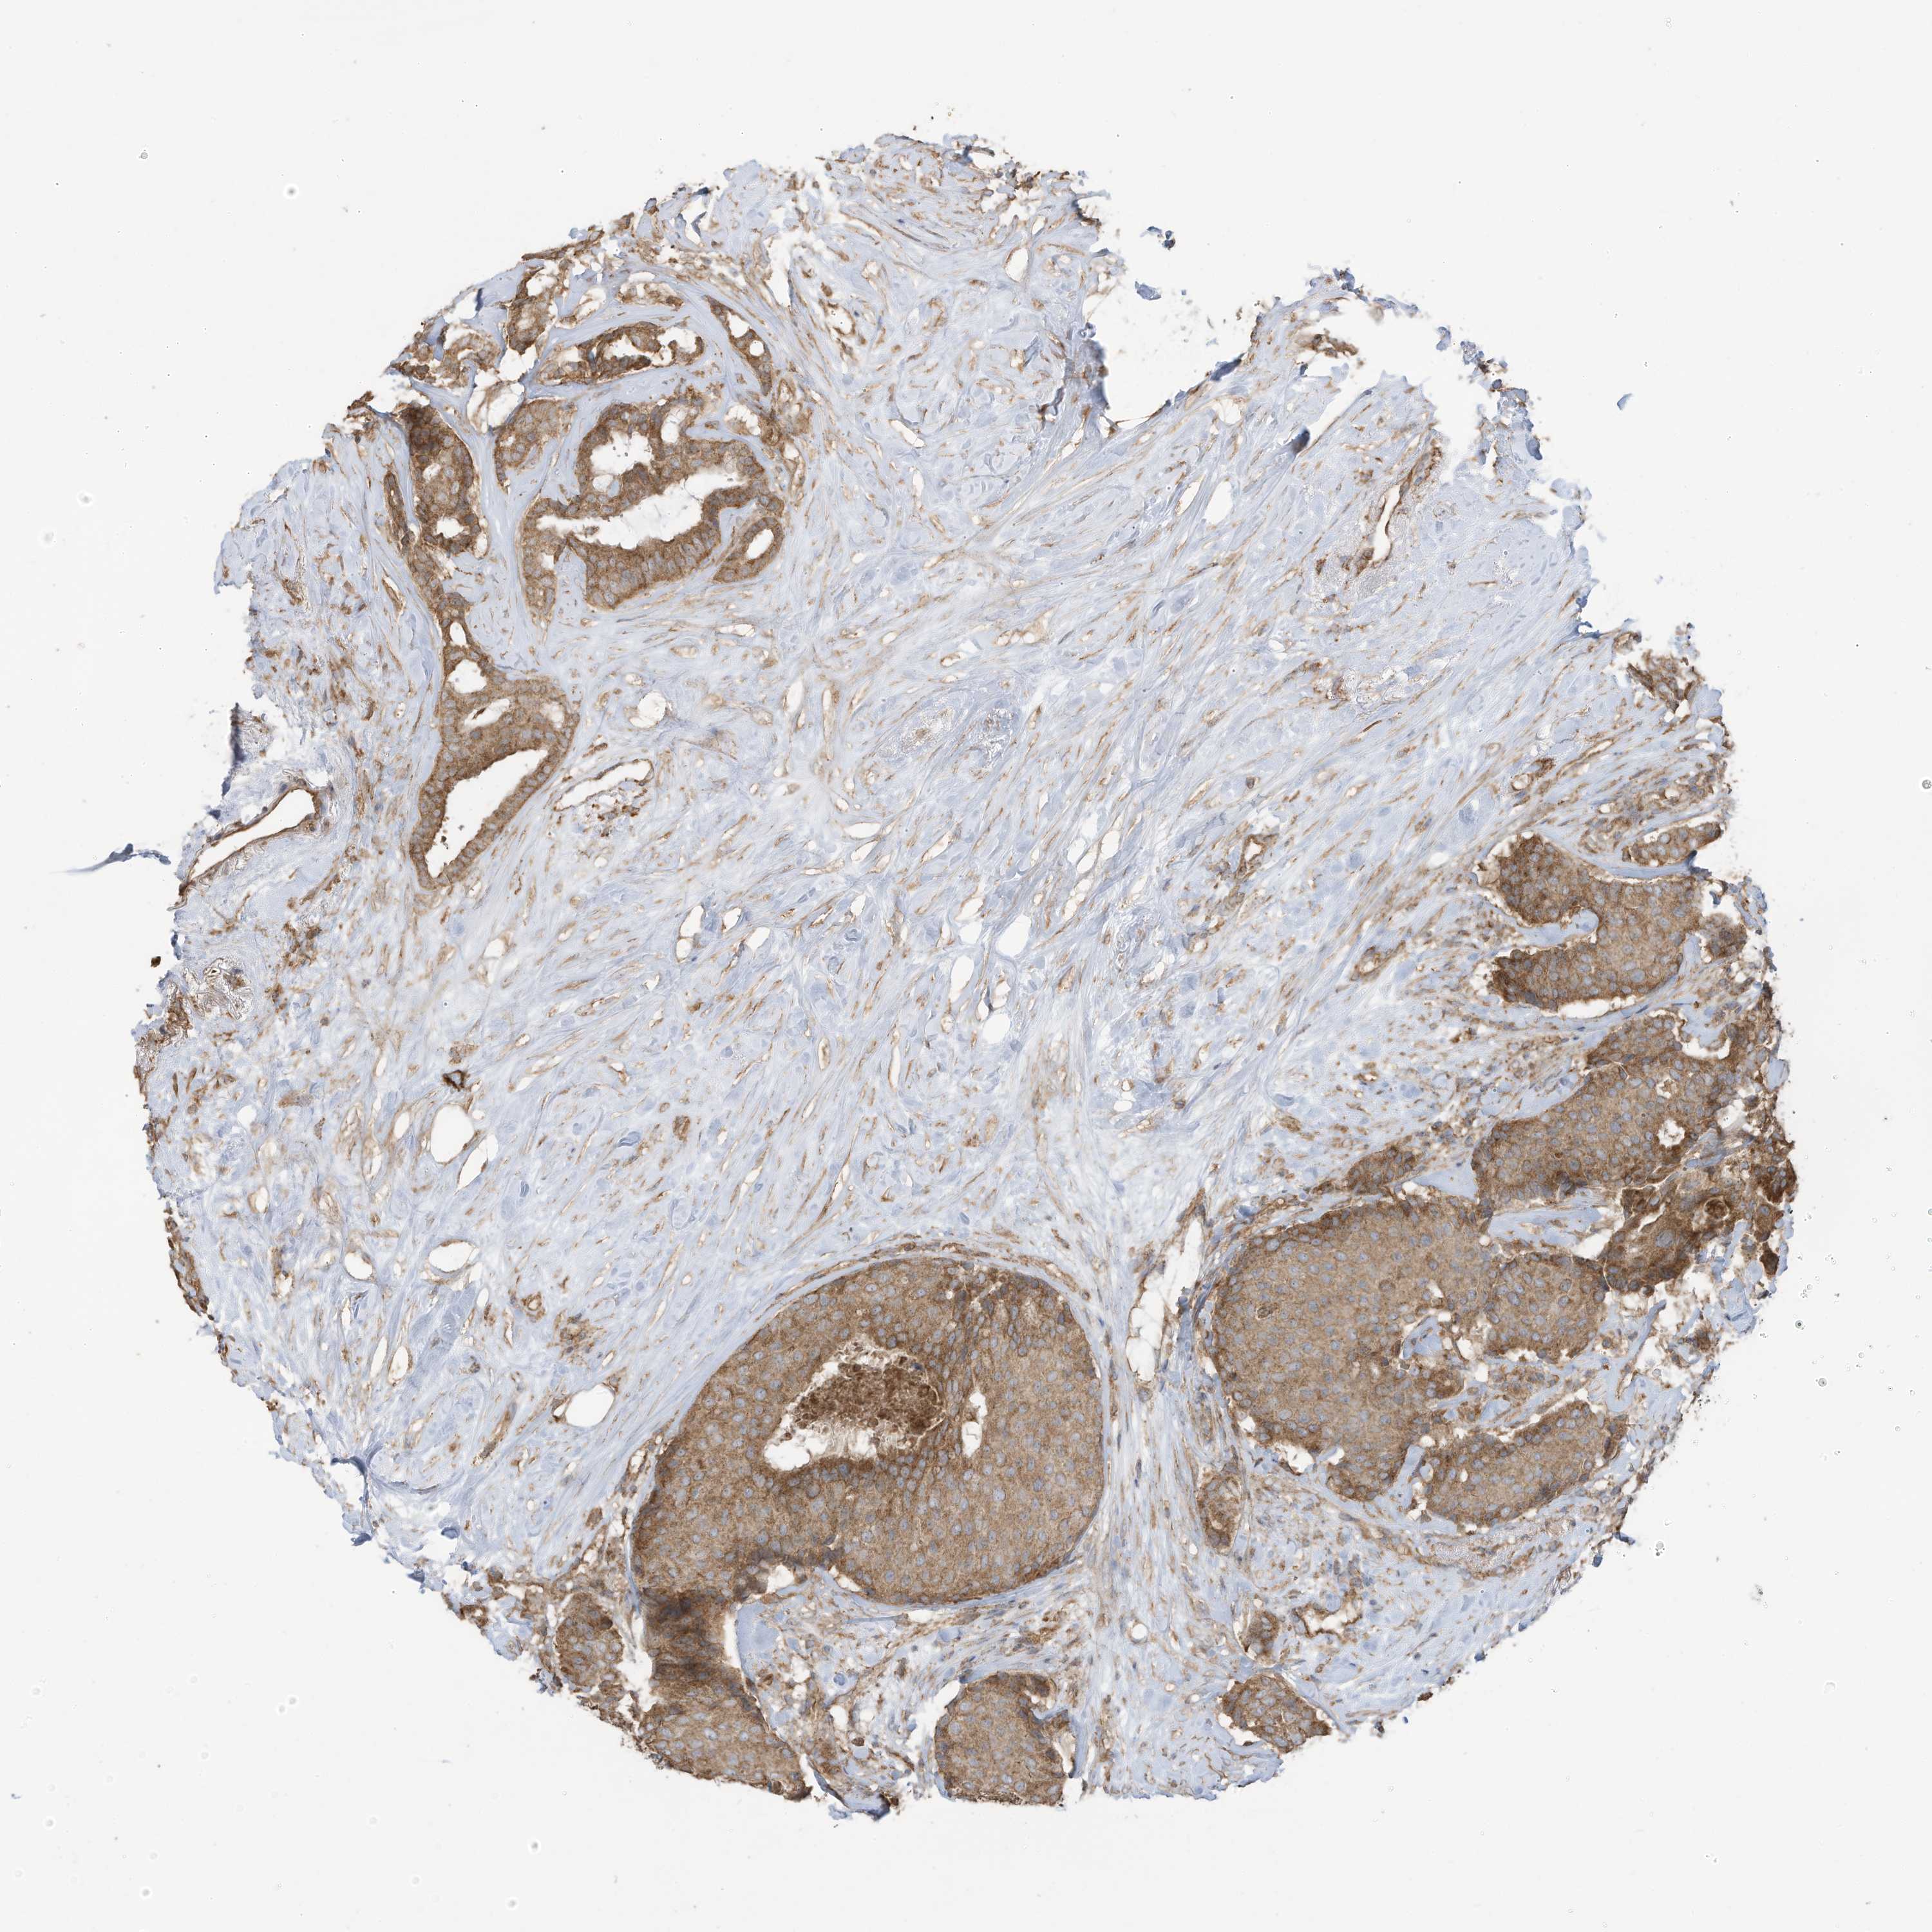

CANCER BREAST CANCER Show tissue menu

BRCA TCGA BRCA VALIDATION PROTEIN EXPRESSION